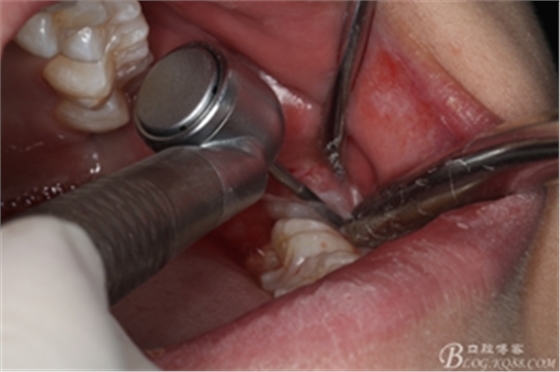

圖6.麻醉效果確定后,在37的近中做垂直松弛切口+遠(yuǎn)中水平切口

圖7. 遠(yuǎn)中的水平切口